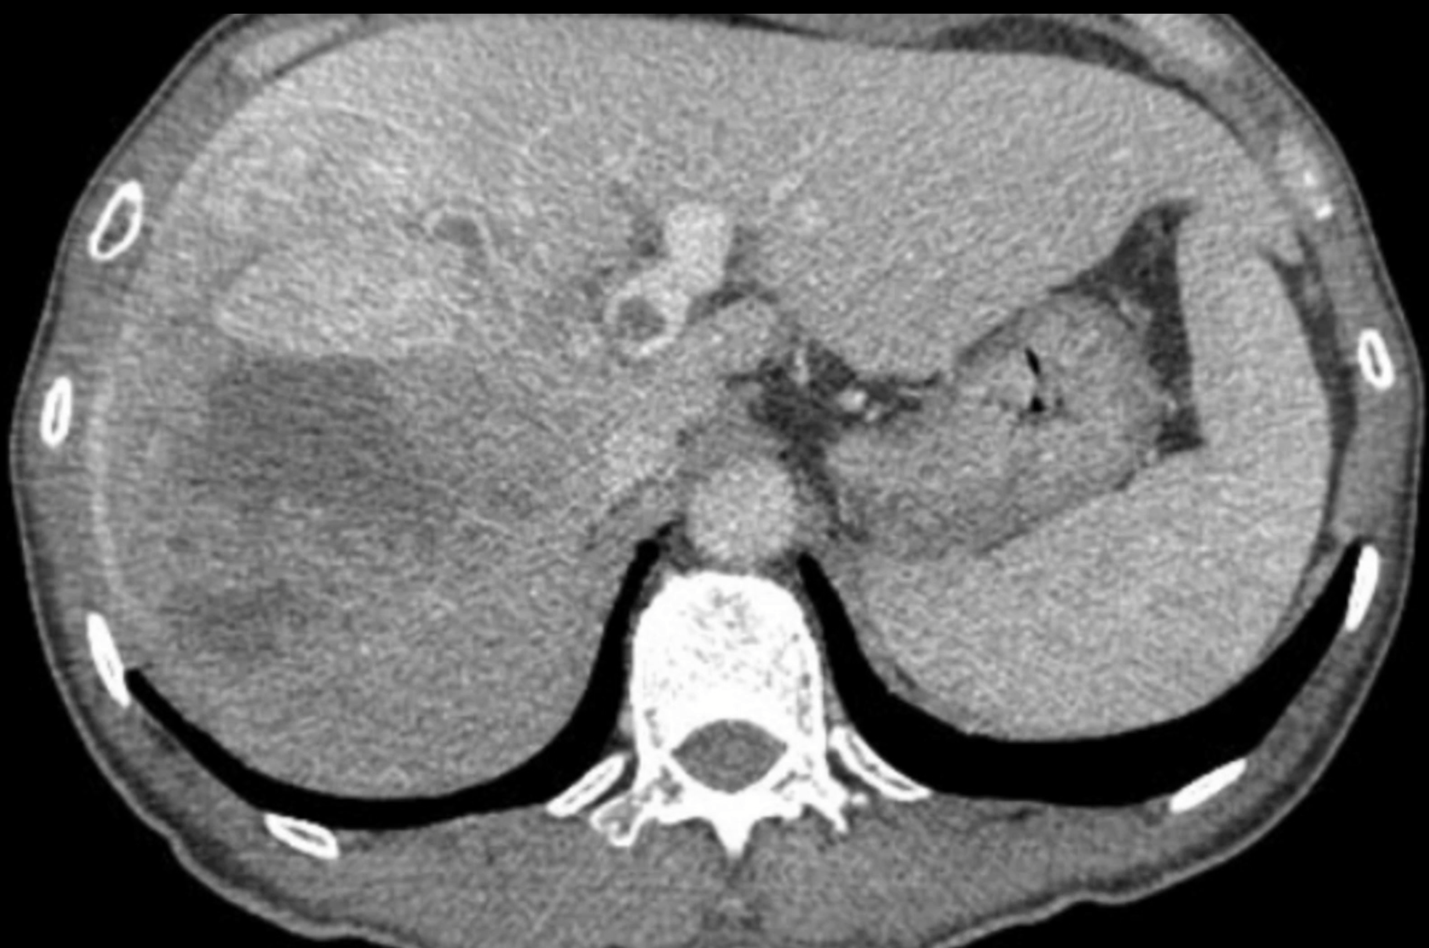

Cách đây 4 năm, bệnh nhân N.T.Đ. (64 tuổi) được chẩn đoán ung thư biểu mô tế bào gan (HCC) gan phải giai đoạn muộn, khối u lớn kèm huyết khối tĩnh mạch cửa lan vào thân chung và lan sang tĩnh mạch cửa trái, trên nền viêm gan B mạn tính và xơ gan. Sau quá trình điều trị tại tuyến dưới, bệnh nhân được chuyển đến Bệnh viện Hữu nghị Việt Đức.

| Hình ảnh phim chụp cắt lớp vi tính cho thấy khối u lớn gan phải kèm huyết khối tĩnh mạch cửa lan vào thân chung và tĩnh mạch cửa trái. |